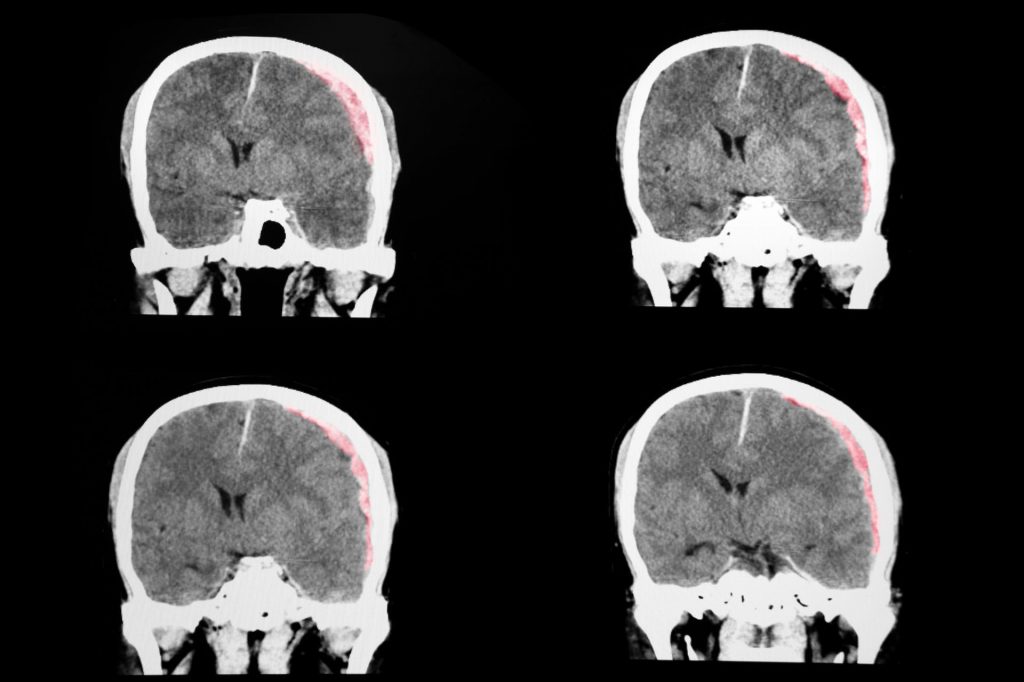

- Imaging (CT or MRI scans), which are usually used to rule out a more serious brain injury

Diffusion-weighted magnetic resonance imaging (MRI) sometimes shows subtle brain changes in people with TBI. Further studies are needed to clarify whether it is useful for the diagnosis of balance problems after TBI.